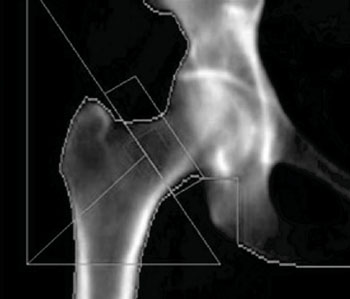

Изображение тазобедренного сустава, полученное при проведении двухэнергетической рентгеновской абсорбциометрии для измерения плотности костной ткани (фото любезно предоставлено доктором Энтони Морроу (Anthony Morrow)).

Ученые из Университета Аквилы (Аквила, Италия) включили в исследование 56 женщин в постменопаузе, страдающих остеопорозом, чей средний возраст составлял 65.39 ± 9.68 лет, и 26 подобранных по возрасту здоровых женщин в постменопаузе в качестве контрольной группы. Измерения минеральной плотности костной ткани (МПКТ) были выполнены с использованием метода количественной ультразвуковой сонометрии пяточной кости и подтверждены измерением в поясничном отделе позвоночника и тазобедренном суставе методом двухэнергетической рентгеновской абсорбциометрии. Как пациенты, так и представители контрольной группы были разделены по возрасту (младше или старше 65 лет) и серьезности заболевания (оценка по Т-балловой шкале (T-score) и наличие переломов).